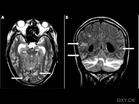

(5)血管炎的影像學診斷:

很多影像學檢查有利於相關血管炎與其他疾病如動脈粥樣硬化與大動脈炎可通過彩超來鑑別:動脈硬化閉塞症患者二維超聲顯示動脈內膜增厚、毛糙,閉塞腔內為大小不等、形態各異的強回聲斑塊堆積,部分顯示為局限的低回聲,形成不同程度狹窄或閉塞,CDFI顯示閉塞管腔內無血流信號,閉塞動脈周圍可見側支循環血流。大動脈炎超聲顯示血管壁長堤狀增厚,呈中低回聲,正常結構消失,管腔呈連續性狹窄或閉塞。重度狹窄時CDFI表現為顏色變暗的纖細狀血流,閉塞段顯示管腔內無血流信號。大動脈炎血管呈向心性變化,動脈粥樣硬化呈偏心性變化。

3)系統性血管炎的診斷需根據臨床表現、實驗室檢查、病理活檢資料及影像學資料包括X胸像、血管造影、CT/MRI等綜合判斷,以確定血管炎的類型及病變範圍。